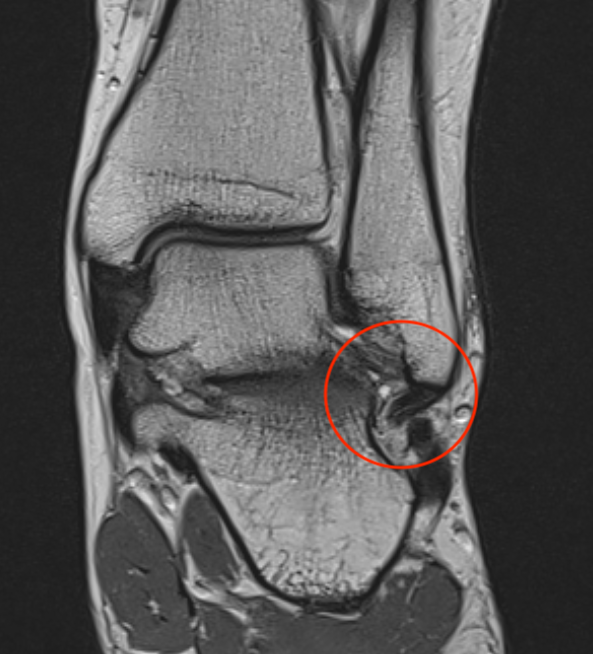

MRI

ATFL tear

CFL tear